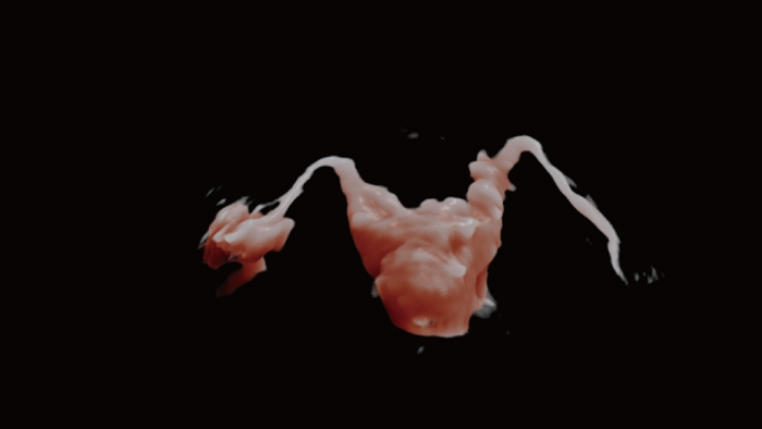

Since the company was founded, Mindray is continuously exploring new ways to improve diagnostic confidence. Powered by the most revolutionary ZONE Sonography? Technology, the ZST+ platform brings ultrasound image quality to a higher level by zone acquisition and channel data processing.

Thanks to the innovative, software-driven ZST+ platform, the Resona series is continuously evolving with the leading-edge technologies to meet the most challenging diagnostic demands in womenŌĆÖs health practice. More importantly, it is designed with the understanding that the wisdom of experts is always precious, and you need more intelligent partner for enhanced speed and confidence. Finally, Resona series with Zone Intelligence provides a total solution to help you with diagnostic confidence, efficiency, and standardization across different diagnostic challenges in todayŌĆÖs demanding and overburden hospital environment.

Advanced Features